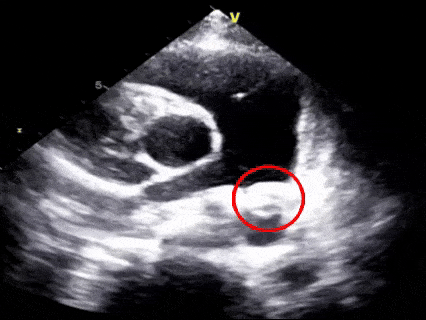

术前超声再次确认

动脉水平可见明显彩色血流